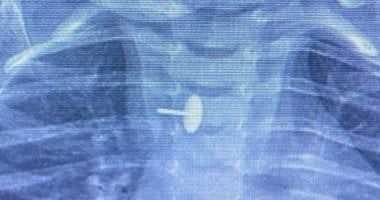

الجمعة، 07 نوفمبر 2025 01:49 صنجح فريق قسم جراحة الأطفال، بمستشفى الأطفال التخصصي ببنها، بمحافظة القليوبية، بقيادة الدكتور محمد متولي رئيس قسم جراحة الأطفال، في إجراء عملية دقيقة لاستخراج دبوس ضغط من مريء طفلة عمرها سنة و7 أشهر، كانت قد ابتلعته منذ 6 أشهر.

الجسم الغريب استقر داخل جدار المرئكشفت مستشفى الأطفال التخصصي ببنها، في بيان لها، أن الجسم الغريب استقر داخل جدار المريء، مما تسبب في عدم قدرة الطفلة على البلع طوال هذه الفترة، وجعل حياتها في خطر دائم. استخدام أحدث الأجهزة في الجراحة

دبوس ضغط فى مرئ طفلة